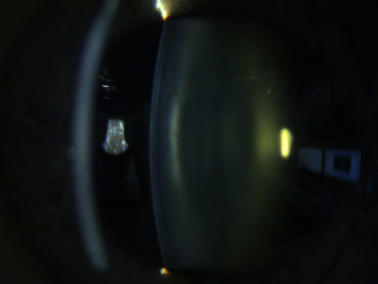

Klare Linse ohne Linsentrübungen

Katarakt („Grauer Star“)

Eine Katarakt (links) verursacht ein unscharfes Bild durch vermehrte Lichtstreuung. Ein Linsentausch (rechts)  korrigiert den Abbildungsfehler.